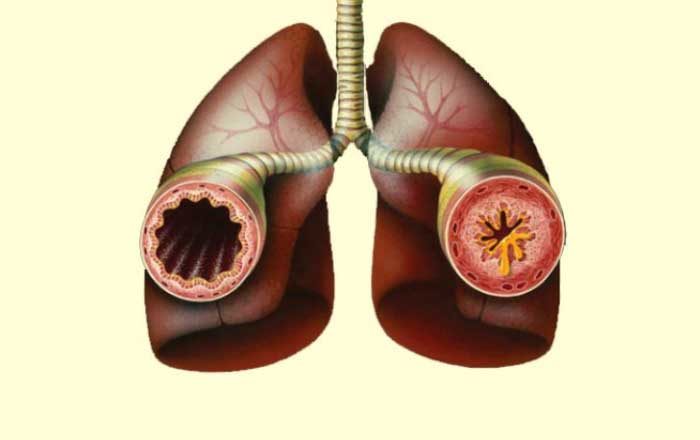

- Astm. La persoanele cu sindromul Churg Strauss care au deja astm, simptomele devin mai agresive și necesitǎ ȋnceperea tratamentului cu steroizi pentru a controla boala. Alte persoane dezvoltǎ ceea ce este cunoscut sub numele de astm cu debut tardiv. Cu toate acestea, boala Churg-Strauss apare foarte rar ca o complicație a astmului.

- Dispnee, astm sau insuficiență cardiacă congestivă

Diagnosticare bolii nu este deloc ușoarǎ, mai ales ȋn condițiile ȋn care simptomele pot fi ușor confundate cu cele date de o altǎ afecțiune. Pentru a ajunge la un diagnostic corect sunt necesare realizarea unor analize de sȃnge, radiografii pulmonare, dar și o eventualǎ biopsie a organului afectat.

- Inflitrate pulmonare pe radiografia pulmonarǎ